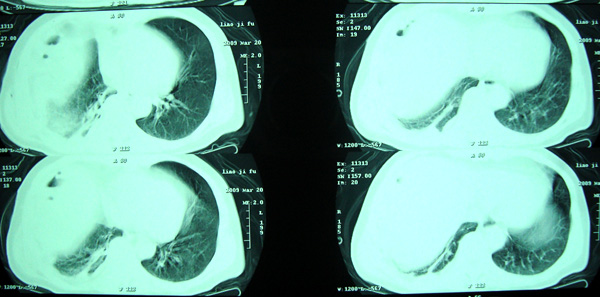

经治疗至17日胸闷痛摄片如9号图,20日复查如7,8号片.

结论:右侧大量胸腔积液,可疑膈下脓肿.

20日院外ct检查,片示于后.

1)考虑右肺感染性病变(化脓性肺炎或肺脓肿可能)。2)右侧液(脓)气胸,部分包裹。

考虑1、右膈下脓肿并肺脓肿,2、右侧液气胸

右肝上间隙积液,支持考虑膈下脓肿,

右侧脓胸、右膈下脓肿。不除外右肺化脓性肺炎。

右侧膈肌抬高明显,胸腔内无明显积液,表现为胸膜反应,肝脏周围大量积液,并见多个液气平面。右下肺不均匀密度增高影。结合临床考虑右侧膈下脓肿并腹腔内积液、右下肺并发感染及胸膜反应,节段性肺不张不除外。

右侧肺脓肿,右侧包裹性脓气胸

右肺下叶见大片状病灶,密度不均,其内见透光区。沿右侧胸壁见多发含气腔,其间可见间隔,其内部分可见液平。膈肌下未见异常(纵隔窗窗位太低)。应该是典型的化脓性肺炎合并脓胸。

右隔下积脓并右侧肺脓肿;右侧液气胸